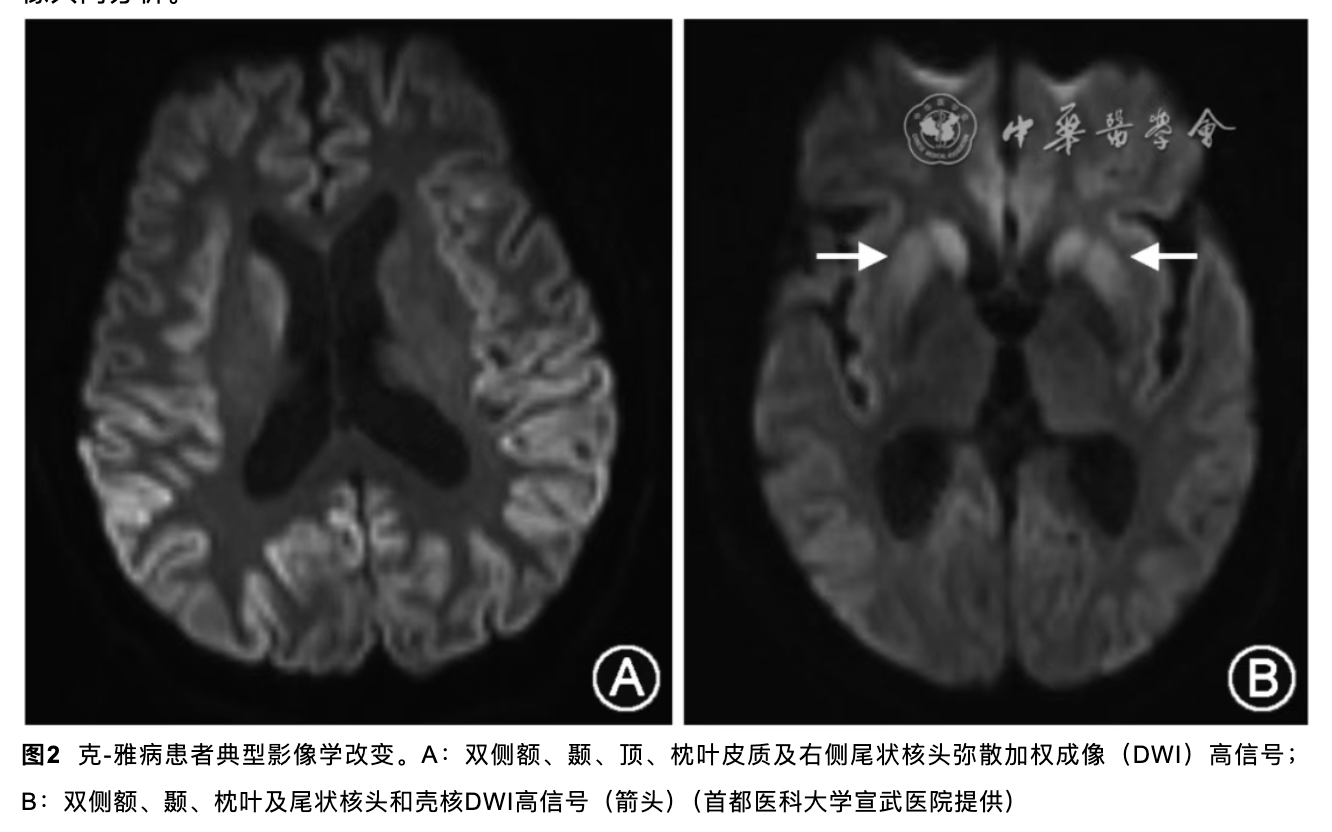

神经内科梁主任会诊后认为:患者二月前出现头晕,症状加重,一月前出现精神症状当地头颅MRI示左侧尾状核和枕叶DWI高信号,本院复诊尚可见硬脑膜强化意见,建议床边脑电图,复查腰穿查脑脊液RTQUICE排除克雅氏病可能。查血LGI1抗体,继续甲强龙治疗。随后送的LGI1抗体结果阴性,而脑脊液的RT-QuIC结果为阳性,因此诊断为克雅病。

可以参考指南克-雅病中国诊断指南2021

本案例的突破点在于病史+脑MRI检查结果,对比指南可以看到我们的MRI在尾状核那边也有明显强化的表现。